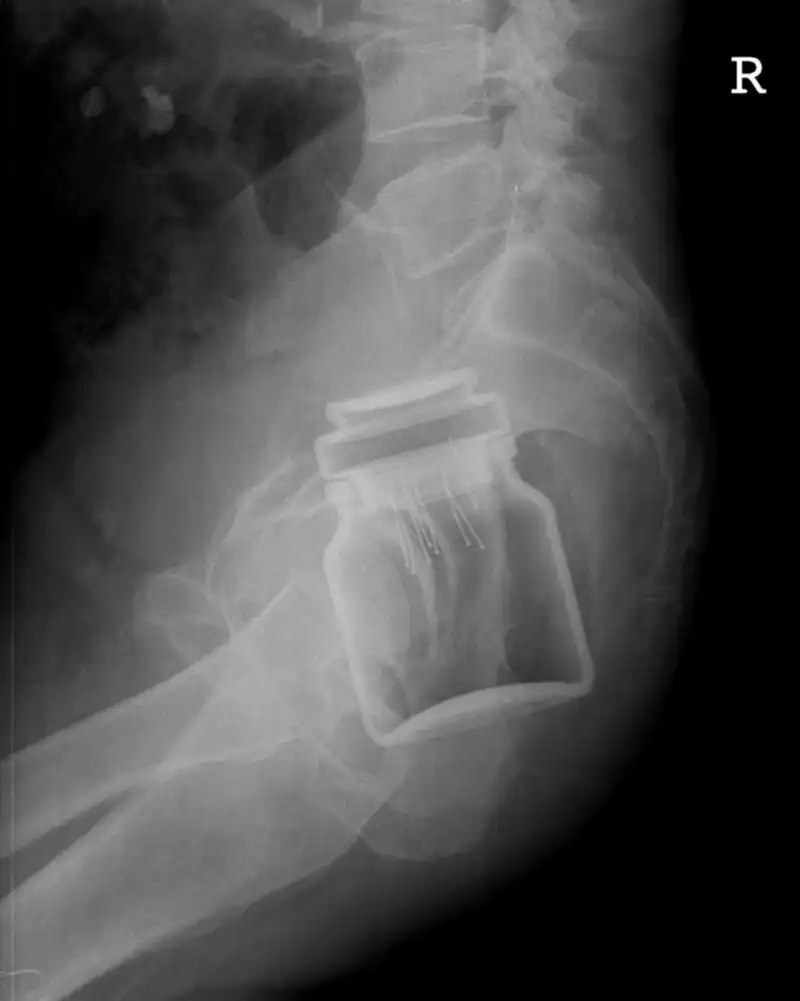

Может, была Пасха?